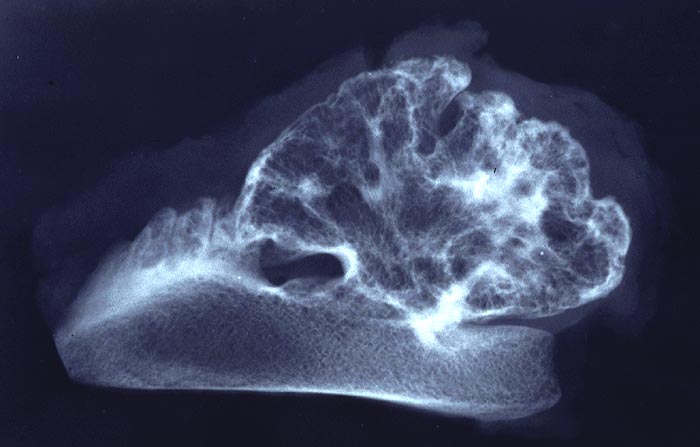

Im konventionellen Röntgenbild lassen sich gestielte und breitbasige Osteochondrome unterscheiden, wobei letztgenannte Formen immer vom Gelenk weggerichtet sind. Ein wichtiges Charakteristikum ist, dass die Spongiosa des Osteochondroms mit der Spongiosa des ortsständigen Knochens in Verbindung steht und die Läsion nicht einfach nur der Kompakta aufsitzt. Die Knorpelkappe ist im konventionellen Röntgenbild (> 5033) nur angedeutet erkennbar, kann aber im CT, MRI oder im Ultraschall dargestellt und ausgemessen werden. In der Mehrzahl der sporadischen aber v.a. der hereditären Osteochondrome lassen sich biallelische Inaktivierungen des EXT1 oder EXT2 Gens nachweisen, was die neoplastische Genese der Läsionen unterstreicht.